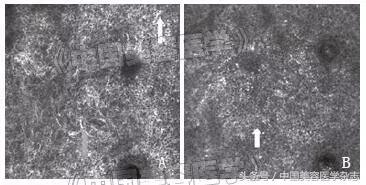

注:A.治疗前,RCM下基底层色素增多,亮度高(黄色箭头所示),可见树突状细胞(红色箭头所示);B.治疗后,RCM下基底层色素减少,亮度低(黄色箭头所示),未见明显的树突状细胞。

图2 治疗前后RCM下的改变